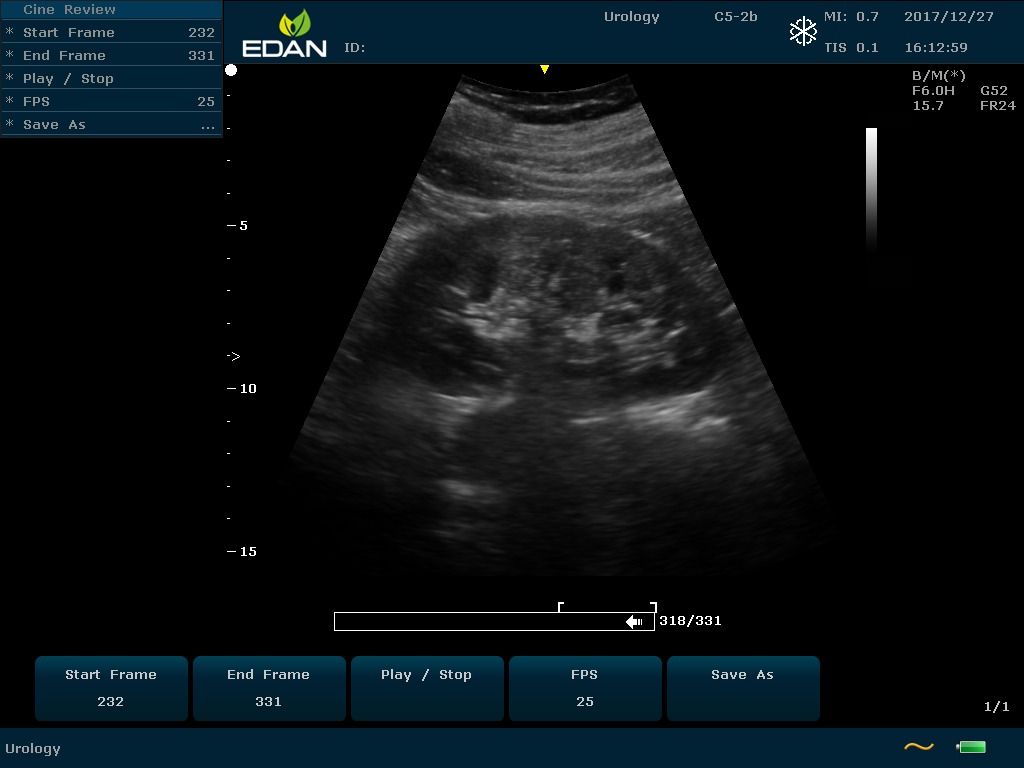

Особенность U60 Edan — расширенное применение. Ультразвуковой аппарат рекомендован для абдоминальных исследований, гинекологии и акушерства, кардиологии, педиатрии, урологии, изучения малых органов, сосудов. Для U60 Edan используются конвексные, линейные, фазированные и внутриполостные датчики.

Передовые технологии позволяют повысить качество визуализации в несколько раз. УЗИ-аппарат U60 Edan отличается возможностью быстрой настройки визуализации. Специальные функции позволяют моментально отображать данные за счет быстрой оптимизации параметров. Режимы визуализации: B-mode, M-mode, Color Doppler, Power Doppler Imaging, Pulsed Wave Doppler, Continuous Doppler.